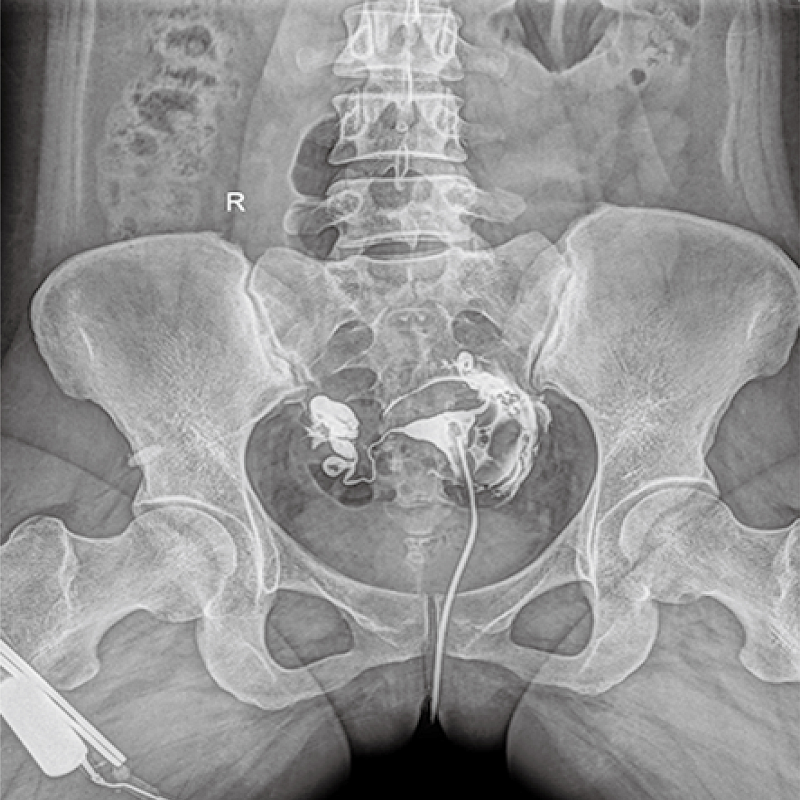

Clinical picture

臨床圖片